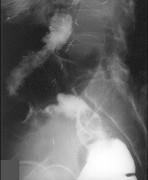

问题 女,50岁,便血10余年,加重1年(连续出血),近2个月大便时肛门常滴鲜血,量较多,X线检查如图,最可能的诊断是()

选项 A.直肠癌 B.直肠绒毛状腺瘤 C.直肠淋巴瘤 D.直肠转移瘤 E.直肠结核

答案 B